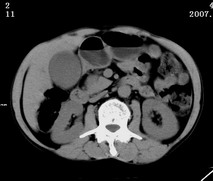

以下是引用zjzjr在2007-9-15 22:24:00的发言:[br]胰头钩突略饱满,肝内外胆管略扩张,胆囊积水.建议增强扫描.

以下是引用代课学生在2007-9-16 10:20:00的发言:[br]胆总管中段以上胆管均示扩张,考虑胆总管下段/胰头部病变,建议增强或micp检查。